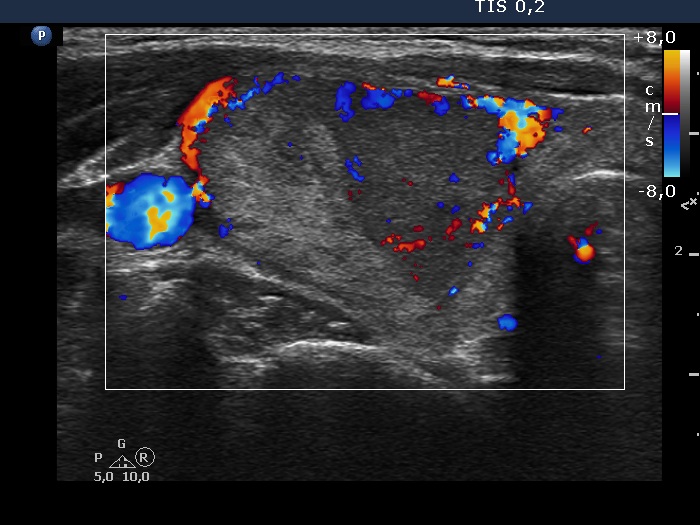

Ultrasonography. The thyroid was echonormal. There was a heterogeneous nodule in the right lobe. The lesion contained roughly equal proportions of echonormal and moderately hypoechoic portions. The nodule had a thin halo and presented perinodular blood flow.